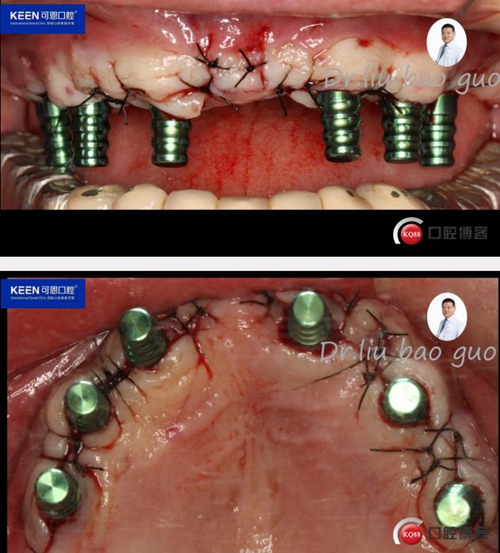

手術(shù)過程

(因設(shè)備限制,未能實(shí)現(xiàn)手術(shù)全程數(shù)字化導(dǎo)板,僅在手術(shù)之前導(dǎo)板定位)